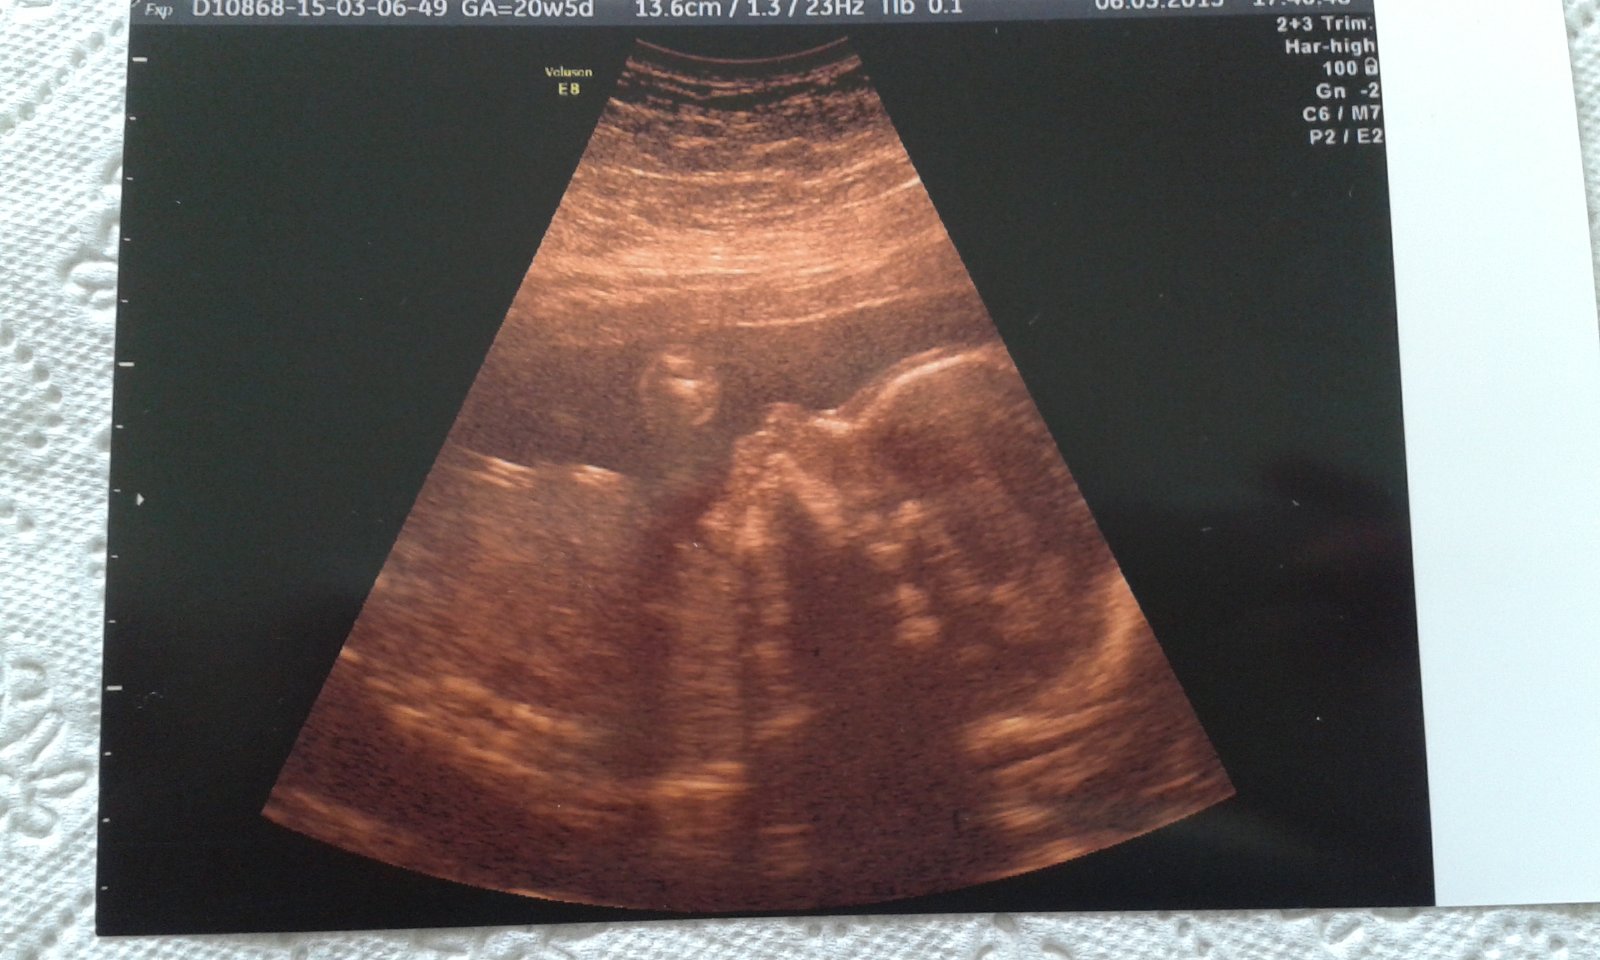

ahojte dievcata,tehulky od vcera mam taky cudny pocit v brusku akoby pnutie alebo tvrdnutie ,neviem to opisat ako ked je napnuty sval a neda sa uvolnit,ale brusko nieje na dotyk tvrde ale z vnutra to citim .Na poradni som bola v utorok a bolo vsetko ok,tak teraz neviem co to je.

@diska aj ja to niekedy mam, take napatie v brusku. ale ja si davam kalcium a magnézium kazdy den, lekar mi vravel, ze uskodit to nemoze a dokonca to posilni srdiecko malého. mne to prejde tiez ked si lahnem a oddychnem. segra ale bola na tvrdnutie bruska v nemocnici, ale vsetko dobre dopadlo. ja som teraz 23tt